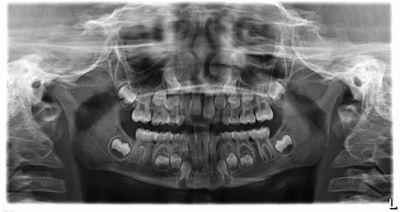

Every orthodontist has a few cases that keep them up at night, where a single tooth seems to have a mind of its own. One recent discussion on the Orthotown message boards centered on a 10-year-old patient (Figs. 1–3) whose upper right canine (UR3) was trying to erupt past the lateral incisor (UR2). The case sparked a lively debate on timing, technique, and just how much Phase I treatment is really worth.

Fig. 1: Current records. 10 years old.